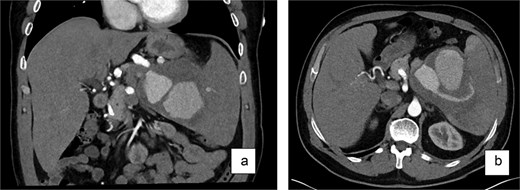

History included a left-hip fracture (bicycle accident, 2 years prior), hypertension treated intermittently with lercanidipine, daily omeprazole, and bi-weekly testosterone injections to enhance fitness performance. He had no history of smoking, alcohol consumption, or pancreatitis and was allergic to amoxicillin. Examination showed a soft abdomen with mild left-upper-quadrant tenderness; the spleen was not palpable. Three-phase contrast CT demonstrated a 10 × 10 × 10 cm partially thrombosed, avidly enhancing lesion at the splenic hilum, displacing the pancreatic tail—features diagnostic of a SAP (Fig. 1).

Contrast-enhanced CT scan (a—coronary view, b—axial view) of the abdomen revealed a large, partially thrombosed lesion measuring ~10 × 10 × 10 cm located at the hilum of the spleen. The lesion exhibited significant contrast enhancement in the arterial phase with peripheral thrombosis and displacement of the pancreatic tail.